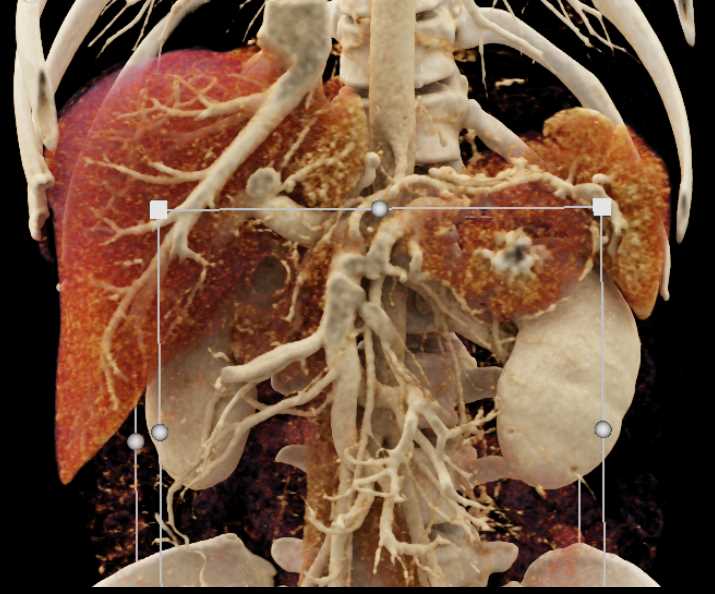

Neuroendocrine Tumor Pancreas